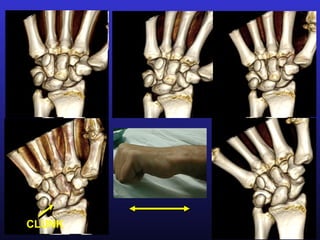

CLUNK

VIDEO

(Please wait)

Non-dissociative Instability- Pathomechanics Non-dissociative Instability  The wrist exhibits a radiocarpal and/or a midcarpal subluxation of the entire proximal row during non- resisted wrist Pathomechanics motion without injury of the interosseous ligaments of the proximal row. Clinical forms  This result in a clunking wrist. Clunking is a low-pitched dull sound produced by sudden subluxation and/or reduction of a partially or totally dislocated carpal bone.  In the clunking non-dissociative wrist the proximal row remains flexed until the wrist is ulnarly deviated at which point it suddenly jumps into extension.

Non-dissociative Instability- Clinicalforms Non-dissociative Instability- Clinical forms  There are two major types of non-dissociated carpal clunking: extrinsec and intrinsec. Extrinsic Clunking  The extrinsec clunking results from injury or bone alteration outside the carpal area (dorsal malunited radial fractures). Intrinsic Clunking  The intrinsec clunking derives from insufficiency or injury of one, or several, carpal ligaments: scaphotrapezoid, triquetrum-capitate-hamate, dorsal Anterior Dorsal Radiocarpal- scaphotriquetral, palmar radiolunate ormidcarpal midcarpal midcarpal ulnolunate.  There are three major patterns of intrinsic carpal clunking: anterior midcarpal, dorsal midcarpal and combined radiocarpal-midcarpal.

Anterior midcarpal clunking The ligaments mostly involved in the palmar midcarpal instability are the scaphotrapezial ligament, and the triquetrum-capitate-hamate ligament.  The proximal row remains tilted palmarly until near the end of ulnar deviation, where it suddenly rotates into 25º extension, sometimes with a palpable thud (catch-up RADIOLUNATE ANGLE clunk).  In most cases there is a combination of medial and lateral ligament insufficiency. 0º Clunk !  There are cases where the dysfunction clearly derives from a predominant injury at the scaphotrapezial ligament (anterolateral midcarpal instability) or from a predominant injury ot the triquetrum-capitate-hamate -25º ligament (anteromedial midcarpal instability). Stress views are recommended to assess the location of the Radial dev Neutral Ulnar dev predominant injury.